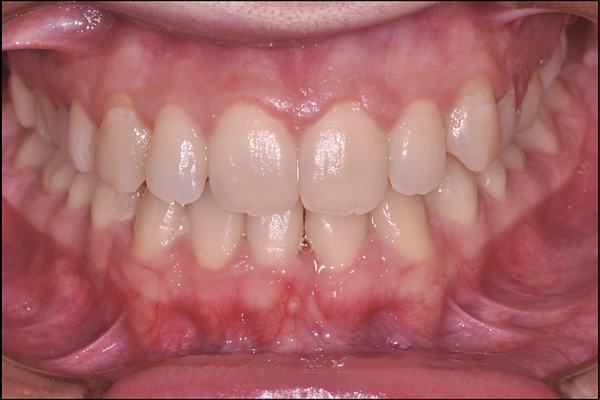

DOPO

Apparecchiatura linguale

La tecnica di apparecchiatura linguale permette di allineare i denti con un apparecchio dal lato INTERNO dei denti, quindi COMPLETAMENTE INVISIBILE. L’ apparecchio è fisso e viene attivato da me durante le visite periodiche. Può essere applicato sia all’ arcata superiore sia a quella inferiore e può prevedere l’ utilizzo di attacchi LINGUALI oppure la tecnica senza attacchi o bracketless.